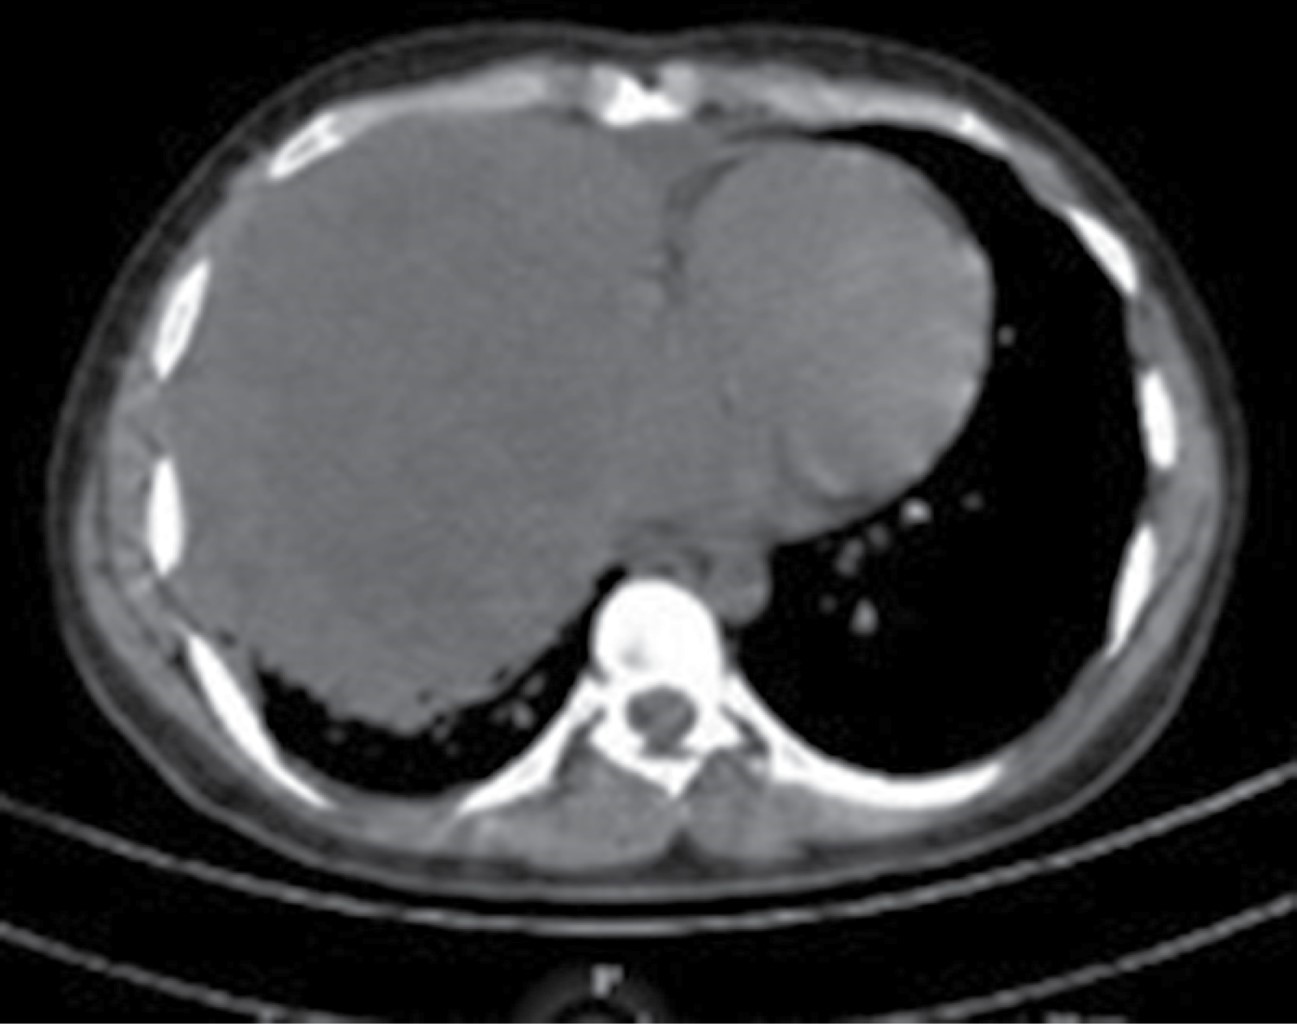

Masculino de 22 años sin antecedentes crónico-degenerativos. Inició padecimiento con tos, no cianozante, no emetizante. A los dos meses de evolución acudió a médico facultativo donde sospecharon de infección viral; a las dos semanas persistió con tos acompañada de hemoptisis, ortopnea, se agregó diaforesis nocturna, pérdida de peso de 7 kg en tres meses, fiebre de 39 °C. Al no mejorar la sintomatología, se le realizó radiografía de tórax, encontrando incidentalmente masa mediastinal. Posteriormente, tomografía de tórax, abdomen y pelvis revela tumoración de mediastino anterior de 14 × 13 cm en hemitórax derecho, desplazamiento de estructuras mediastinales hacia hemitórax izquierdo. Por edad y forma de presentación, se sospecha de linfoma (Figura 1A). La exploración física fue compatible con un síndrome pleuropulmonar de condensación; también se encontró adenopatía inguinal derecha de 5 mm, indurada e inmóvil. Se solicitaron laboratorios, destacando anemia grado 2, plaquetas 622,000/mm3, deshidrogenasa láctica 645 u/L, leucocitos 9,000/mm3, glucosa 92 g/dL, creatina 0.9 mg/dL, albúmina 3.9 g/dL, panel viral negativo, marcadores tumorales con resultado alfafetoproteína 3,080 ng/mL, antígeno carcinoembrionario 0.98 ng/mL, hormona gonadotropina coriónica humana 0.78 ng/mL. Ultrasonido testicular con quiste simple en cabeza de epidídimo izquierdo de 1 mm. Durante su hospitalización, se le realizó biopsia mediastinal por cirugía cardiotorácica en conjunto con resección de masa tumoral por toracotomía; durante el evento transquirúrgico presentó hemorragia masiva de 4,000 mililitros con estado de choque hipovolémico grado 4 que amerita transfusión masiva; se logra resección en fragmentos de masa mediastinal (Figura 1B). Hallazgos posquirúrgicos, masa mediastinal de 12 × 10 cm con fragmentos mayores de 1 cm en tórax por estar adheridos a hilio pulmonar y, representando mayor riesgo de sangrado, amerita colocación de sonda pleural derecha de 36 fr. Posterior a procedimiento de resección tumoral subóptima, remitió la tos, ortopnea, hemoptisis y alzas térmicas; al tener buena evolución clínica, se egresó al paciente (Figura 2). Los hallazgos encontrados en la biopsia resultaron compatibles con tumor germinal mixto tipo seno endodérmico 70%, seminoma 25%, carcinoma embrionario 5% con necrosis tumoral extensa de 50% de la pieza quirúrgica (Figura 3). La inmunohistoquímica resultó en SALL 4 positivo difuso, OCT3/4 negativo, AFP positivo focal, D2-40 positivo focal (1%), PLAP positivo focal (5%), CEA-CD30 negativo. Fue valorado por el servicio de oncología médica, que otorgó quimioterapia con bleomicina, etopósido, cisplatino en cuatro ciclos; y también seguimiento por los servicios de neumología, cirugía cardiotorácica, oncología médica donde, después de cinco meses de evolución posquirúrgica y con tomografía de tórax de control, el paciente permanece asintomático, con seguimiento por consulta externa multidisciplinar por riesgo de compresión de estructuras circundantes y nueva recaída.